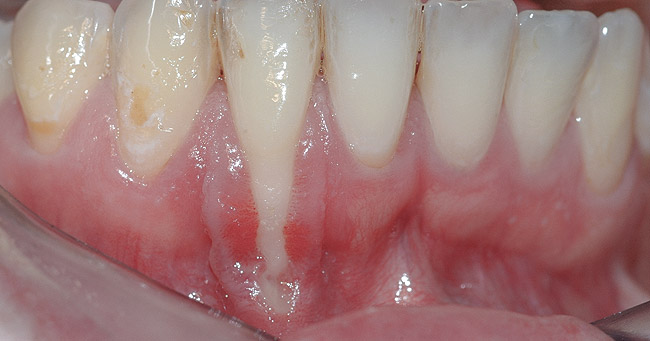

CASE 2 Fig 4. Post-orthodontic Miller Class II recession for which orthodontic treatment was not recommended. Clinical view 3 years after orthodontic treatment, showing relapse in teeth alignment and GR on lower left central incisor.

Figure 4

In cases with thin lingual bone, as measured on CBCT (<2.5 mm at a level of 8 mm apical to the CEJ), orthodontic treatment is not advisable, leaving surgical root coverage as the only option. However, the prognosis for this procedure is poorer, because the predominant cause is not addressed. Figure 4 shows the frontal clinical view of a patient with a hyperdivergent growth pattern who presented with post-orthodontic GR of a labially displaced lower central incisor. The sagittal CBCT view (Figure 5) shows complete absence of lingual bone, which contraindicated orthodontic tooth repositioning.